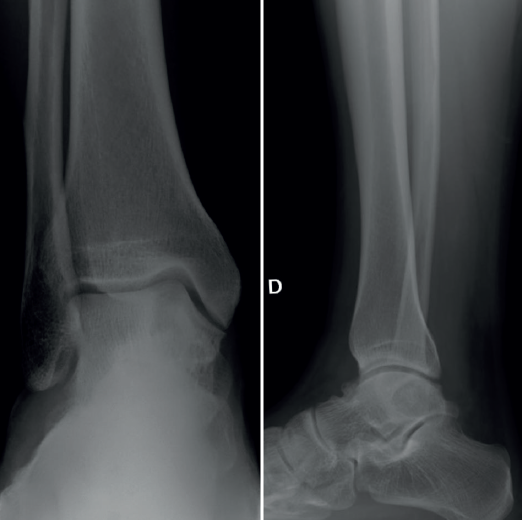

Se presenta el caso de un varón de 33 años con clínica de dolor y limitación funcional en el tobillo derecho de 3 años de evolución. Los estudios por imagen mostraron una lesión de tipo quístico de 2 × 1 ×2,3 cm (diámetros anteroposterior, transversal y craneocaudal), de márgenes geográficos, en el cuerpo del astrágalo, con extensiones filiformes a la articulación tibioastragalina, a nivel de la cúpula medial, que fue orientado en las pruebas radiográficas iniciales como un posible ganglión intraóseo (Figura 1).

Figura 1. Estudio inicial por radiografía simple en carga del tobillo derecho, donde se aprecia la lesión intraósea del astrágalo.